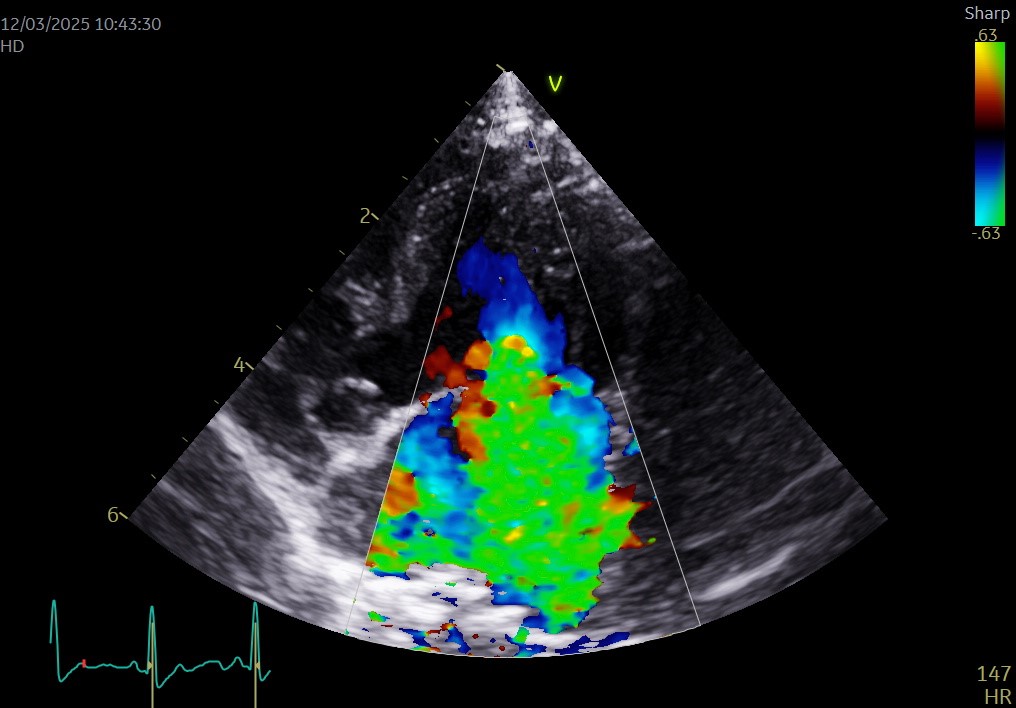

▲心エコー(左心尖長軸四腔断面像)(術前)

心臓超音波検査では僧帽弁閉鎖不全症とそれに伴う心拡大が確認されました(LA/Ao 2.0)。

手術直後は血圧、心拍数、点滴量や尿量など循環を細かく整えて心臓が回復するのを待ちます。不整脈や出血がないことを確認し、超音波検査を繰り返して心臓の変化に合わせて点滴や内服を調整します。